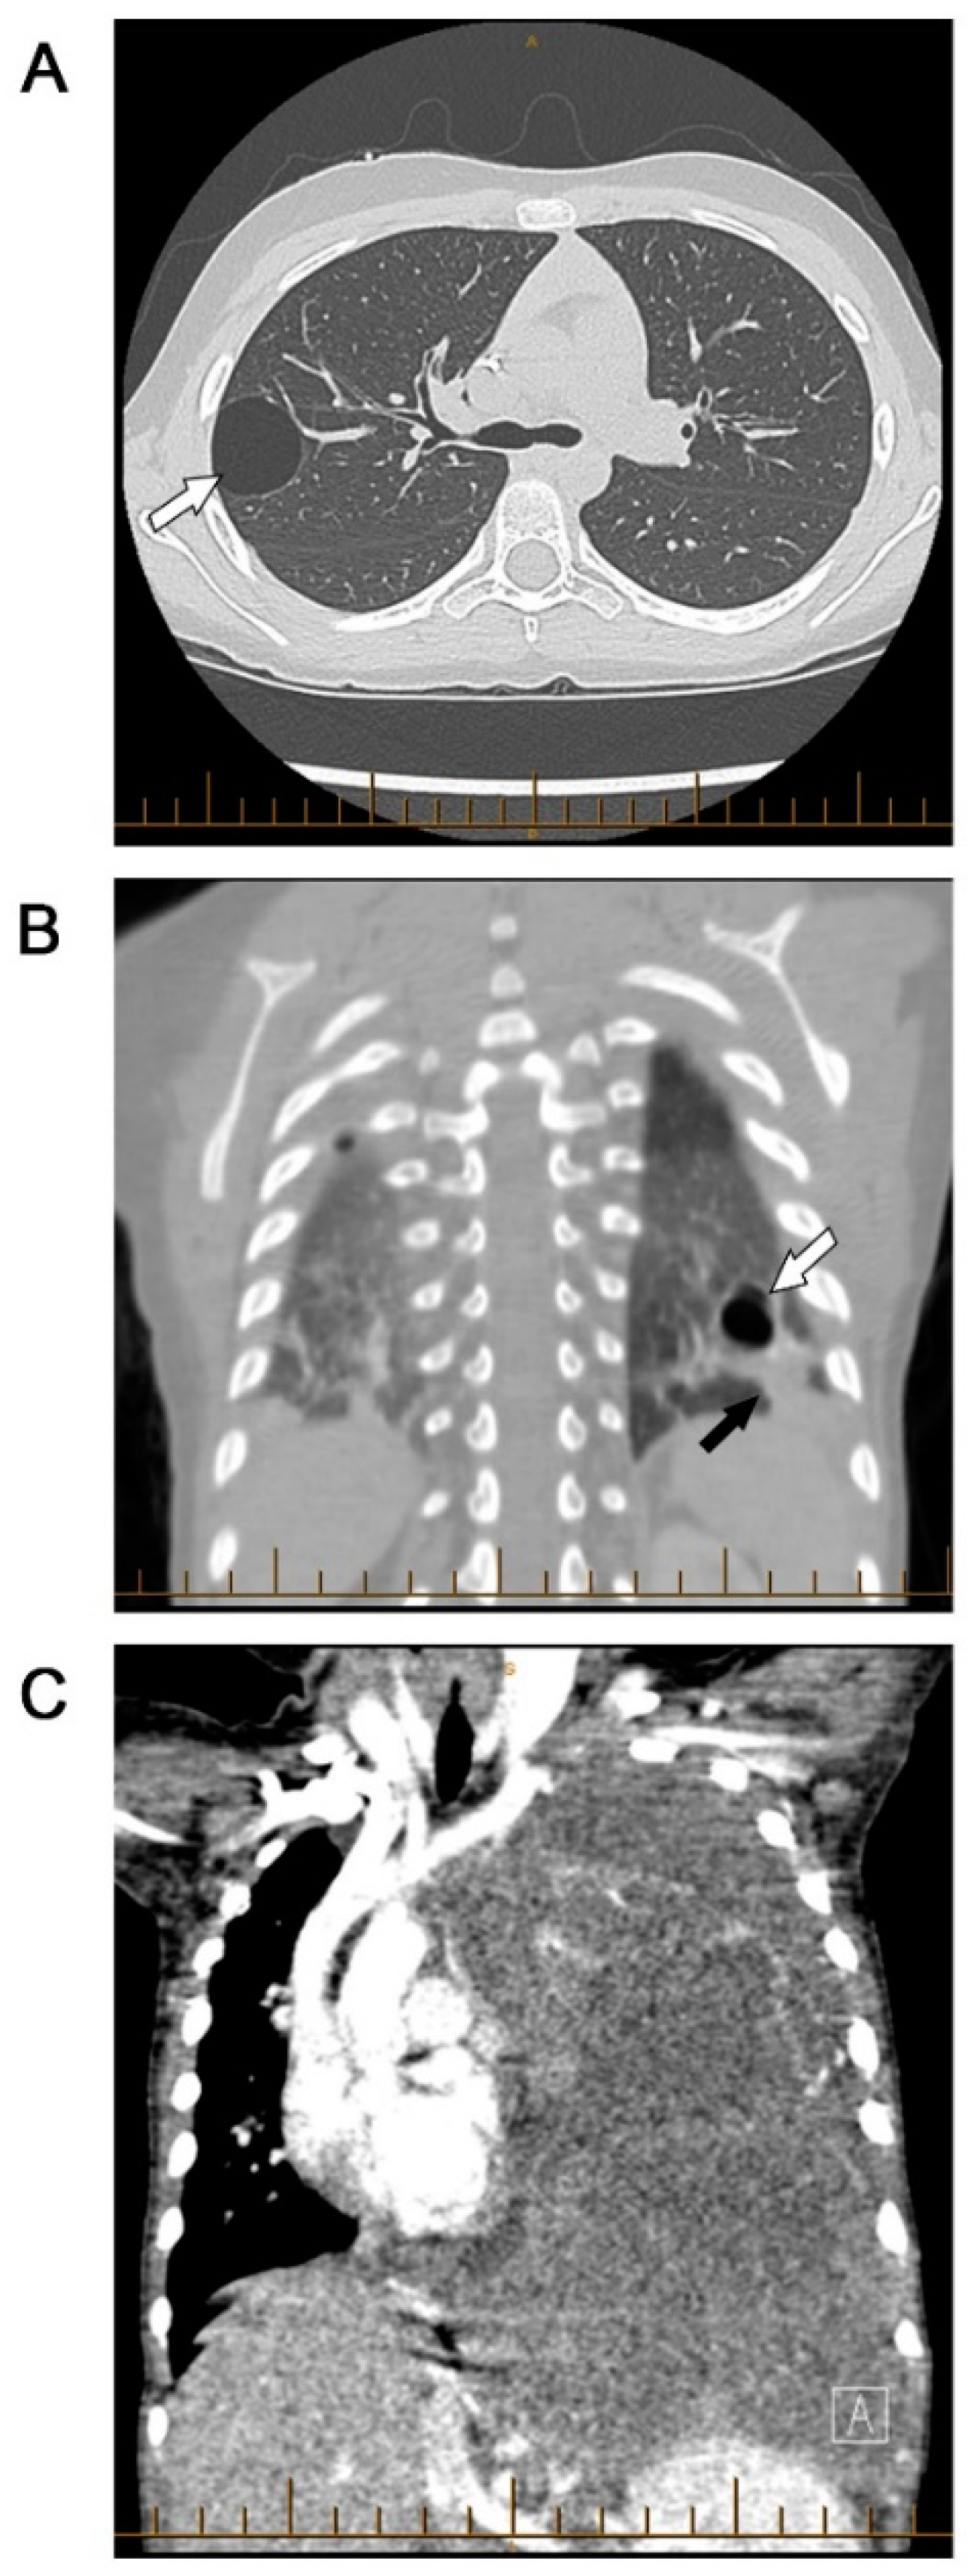

Type III PPBs (purely solid) present at a more advanced age, with a median age-of-diagnosis of 41 months, and do not appear to be seen before 12 months of age. Type III PPB are entirely comprised of tumor cells without intervening cystic spaces. The solid regions in types II and III PPBs are histologically similar, displaying a mixed, sarcomatous pattern. These sarcomatous cells may include interspersed foci of anaplasia, features of embryonal rhabdomyosarcoma, chondrosarcoma, or necrosis. Rarely, progression of necrosis may be sufficient to produce pseudocysts in some type III PPBs, but this does not ‘de-escalate’ a tumor to type II status [1,2,3]. Given this histologic similarity between types II and III, care must be taken to obtain adequate specimens during biopsy to capture the cystic component present in type II PPB (Figure 1).

Figure 1.

Types of pleuropulmonary blastomas (PPB) (A) Type I purely cystic PPB (white arrow). (B) Type II PPB with cystic (white arrow) and solid (black arrow) components. (C) Type III purely solid PPB occupying the entire left hemithorax.